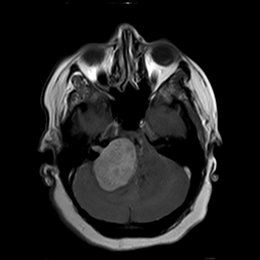

¿Cuál es el diagnóstico más probable de la siguiente imagen?

A)

quiste aracnoideo

B)

Quiste de la bolsa de Rathke

C)

craneofaringioma

D)

Silla turca vacía

E)

macroadenoma hipofisario